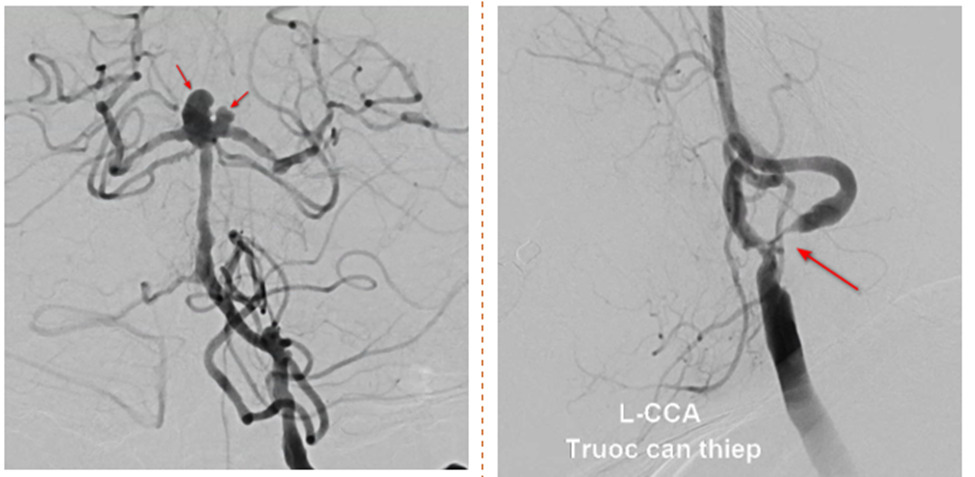

Bệnh viện Đa khoa quốc tế S.I.S Cần Thơ vừa tiếp nhận và can thiệp thành công ca bệnh bít túi phình mạch máu não cổ rộng 2 thùy. Ca can thiệp gặp khó khăn khi bệnh nhân tổn thương hẹp nặng động mạch cảnh trong trái và túi phình xảy ra cùng lúc, do đó việc điều trị cần triệt để cho cả 2 vấn đề.

Điều bất ngờ là mặc dù triệu chứng của bà M. là nhồi máu não, nhưng sau khi chụp MRI các bác sĩ lại phát hiện thêm nguy cơ xuất huyết não do phình mạch còn nguy hiểm hơn. Kết quả chụp MRI não thấy rõ tổn thương hẹp gốc động mạch cảnh trong 2 bên và túi phình đỉnh động mạch thân nền và động mạch tiểu não sau dưới, với kích thước là 4.5x5mm và 3x3mm, trên nền nhồi máu cơ tim cũ đã stent, tăng huyết áp, thiếu máu mạn mức độ trung bình – bệnh thận mạn giai đoạn 3 có những đợt cấp tái phát.

Qua hội chẩn, các bác sĩ đưa ra phương pháp điều trị tối ưu cho túi phình cổ rộng, đỉnh động mạch thân nền của bà M. chính là đặt stent kết hợp thả coil. Tuy nhiên do bà M. cần sử dụng thuốc chống kết tập tiểu cầu nên nguy cơ vỡ túi phình đỉnh động mạch thân nền là rất cao.

ThS.BS Nguyễn Đào Nhật Huy – Đơn vị can thiệp DSA Bệnh viện S.I.S Cần Thơ thông tin, bệnh nhân có tiền sử đang sử dụng thuốc chống kết tập tiểu cầu do nhồi máu cơ tim cũ đã đặt stent từ tháng 1/2023 cũng tại bệnh viện S.I.S Cần Thơ, nhưng vẫn xảy ra nhồi máu não là do tình trạng hẹp gốc động mạch cảnh trong trái quá nặng, đáp ứng kém với thuốc.

Điểm khó ở bệnh nhân này chính là tổn thương hẹp nặng động mạch cảnh trong trái và túi phình xảy ra cùng lúc nên điều trị cần triệt để cho cả 2 vấn đề. Về túi phình thì rất khó để can thiệp nội mạch dẫn đến phải sử dụng stent để hỗ trợ quá trình đặt coil giúp coil giữ ổn định trong lòng túi phình, một kỹ thuật khó trong can thiệp nội mạch.